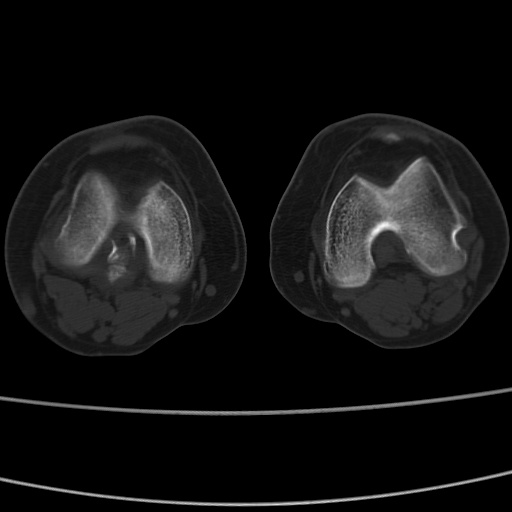

女性,50岁。【请提供患者临床症状体征】

右膝关节退行性改变,关节游离鼠。

右膝关节退行性改变,滑膜黏液囊钙/骨化并游离。

右膝关节退行性改变